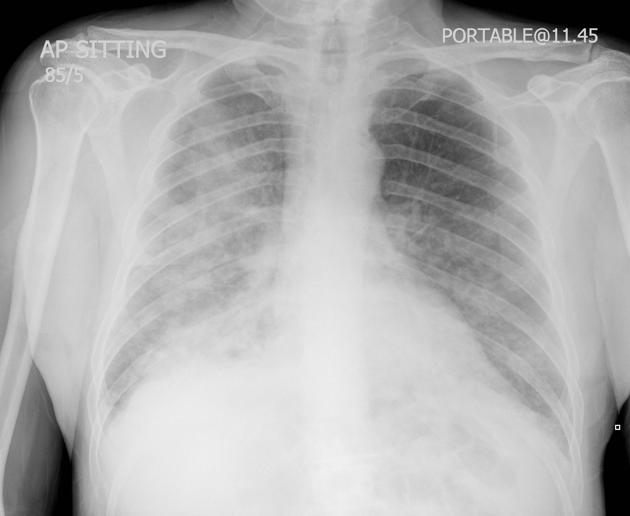

In radiological studies ________ _______ presents as increased attenuation of the lung parenchyma causing obscuration of pulmonary vessels, without significant loss of volume, in the segment(s) affected. Air bronchograms can also be found

Lung Consolidation

(right lower lung consolidation)